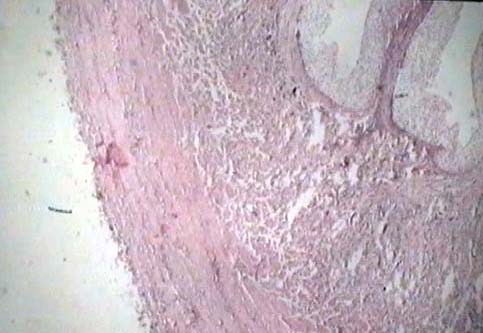

Niere und ableitende

Harnwege

Weiblicher Genitaltrakt